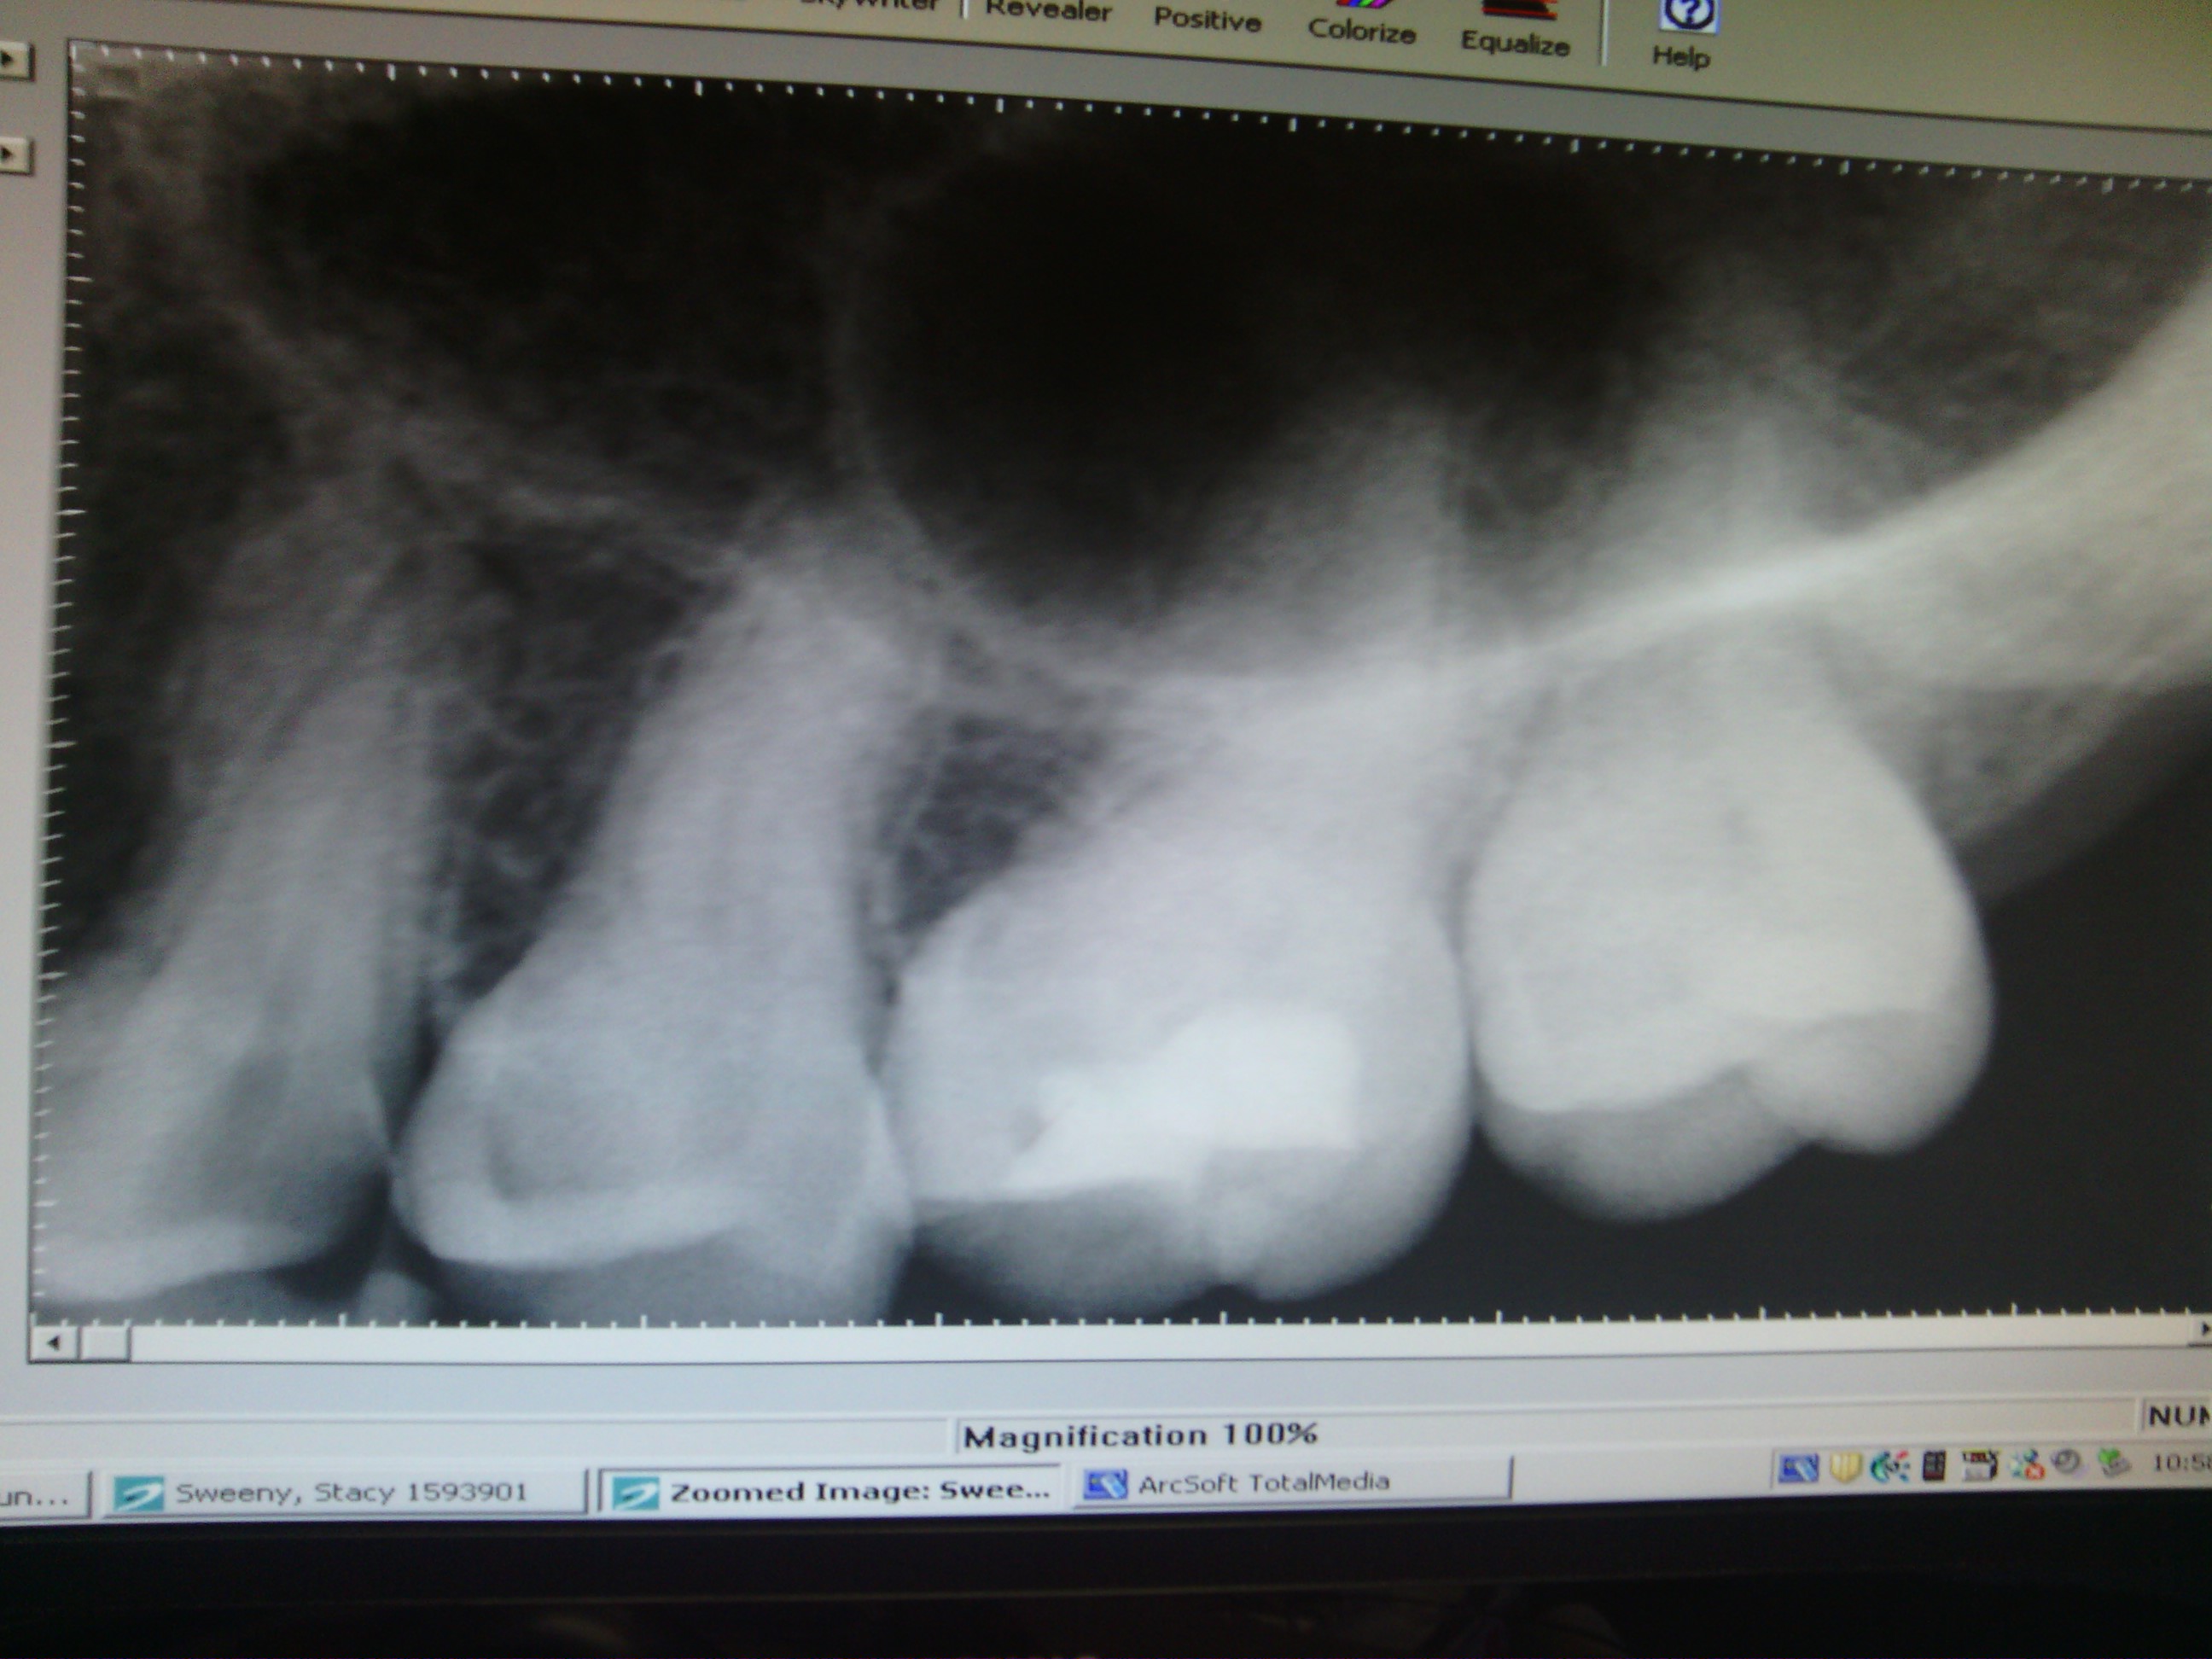

Bright and early this morning I’m getting my first, dreaded root canal on a decaying tooth, and as I look at my black & white dental x-ray in the digital light box, I imagine what my internal organs must look like. My tooth is an enamel coated, cross section picture of death & disease. What’s worse is that I have tried to cure my dead tooth for forty shameful mornings and forty painful evenings, and I forget to factor in the past decades of careless health habits that on most days I’m still unwilling to accept or change. I don’t see animals brushing their teeth or lined up for dental visits. Despite the statistically significant research on diet & nutrition’s impact on health, specifically high fructose corn syrup, our culture is killing us. How are we going to heal that super-sized, spiraling food chain mess? Have you seen the documentary film, King Corn? King Corn is a feature documentary from Independent Lens about two friends, one acre of corn, and the subsidized crop that drives our fast-food nation.

What’s really tough is that I’m a patient with legitimate, physical pain, sitting in Dr. David Fagundes very comfortable dental/medical chair, opening my mouth for a professional stranger, which is very much like opening up about your emotional pain in psychotherapy. “What’s your pain level on a scale of 1-10?” is our fifth vital sign behind temperature, blood pressure, heart rate, and respiratory rate. “A nine. A nine, I talk to myself, because 10 is reserved for birthing grief, a broken femur, third degree burns, or an incurable cancer eating you alive. Ten is reserved for a narcotic addict, looking for their next high. Ten is served when new friends move away like a revolving door and the best you have to offer is a chip of your life and to break bread together as you say good-bye. Ten is reserved for when things don’t go your way and you lose. When you lose heart, and when you lose sight, and like ‘the blind man who stood on the road,’ you cry. Have you read, Dark Night of the Soul? Me either, but I bet this hardcover book bites,” I concluded. “This bites, but the long acting Marcaine® is kicking in to a state of oral, blissful numbness.”